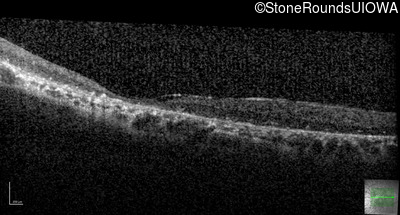

This 41 year old man first came to medical attention at age 18 months when exotropia and amblyopia of his right eye were discovered. At age 11 vitreous strands and retinal vascular sheathing were seen. He has had poor night vision and constricted visual fields since his late teens. Later, at age 44 a traction retinal detachment was noted in his left eye and was treated with a scleral buckle.

Age at visit: 41 years